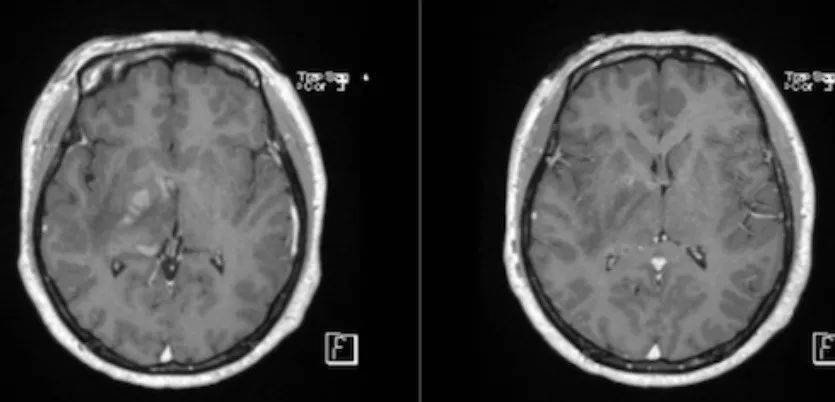

病例8(病例提供: 王浩玥 老师)

患者,女,43岁,因“头晕、行走不稳1月,加重伴左侧肢体无力10天”入院,1月前以“颅内感染、自身免疫性脑炎”收治。激素治疗效果欠佳。1月前增强:

此次复查平扫+强化:

答案:弥漫性大B细胞淋巴瘤

影像表现为:T2/FLAIR显示深部脑白质、皮层、基底节多灶性高信号。常见弥散受限,T2* GRE可见血液产物的“开花征”。T1WC C+多变,通常可见线样和斑片状强化,也可成环形、脑沟样等。脑膜和/或硬脑膜增强。有时类似于血管炎。